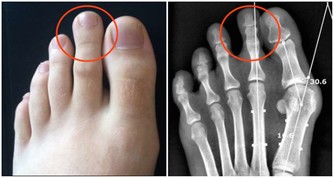

七、腎臟排毒

腎臟是人體最重要的排毒器官,不僅能過濾掉血液中的毒素並使其通過尿液排出體外,還起著保持人體水分和鉀鈉平衡的作用,控制著和許多排毒過程相關的體液循環。尿液中毒素很多,若不及時排出,會被重新吸收進入血液,危害全身健康。

最適合腎臟排毒的時間是早晨5點~7點。身體經過一夜的修復,體液循環代謝的毒素都聚集在腎臟。